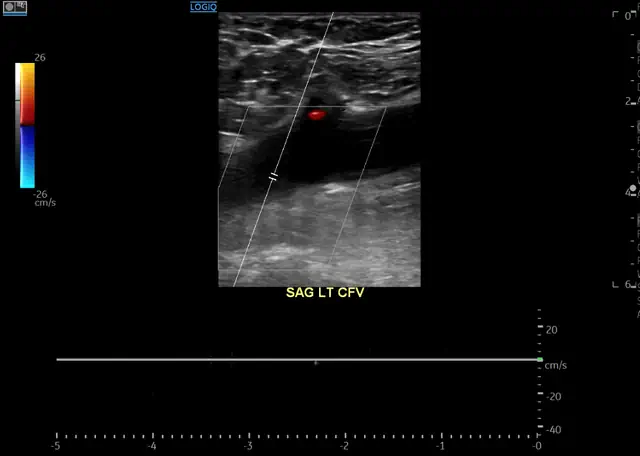

Ultrasound for Blood Clot Diagnosis

The main tool to diagnose a blood clot in a leg vein is ultrasound. The advantages of ultrasound are that it is accurate, safe, cheap and available almost everywhere.

There are three signs of clots that we can identify with ultrasound:

- Visible clot. Basically, this is when we can see the clot. But often we cannot actually see the clot. It is practically invisible on ultrasound.

- Lack of blood flow. Veins are supposed to move blood up toward the heart. But if there is a blood clot in the vein, blood might not be able to flow freely. It is important to remember that some clots do not block flow completely. So even if we can detect blood flow, this does not mean there is nothing in the vein.

- Non-compressible veins. This is the most important finding. Veins are supposed to collapse when we press on them. But if there is clot in the vein, we will not be able to compress the vein. So even if we cannot see the clot, we will know it is there.